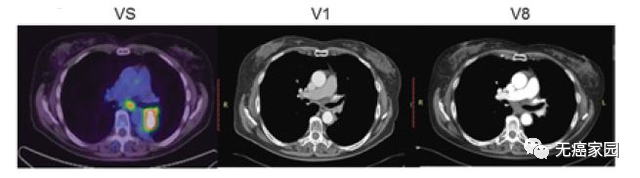

接下来,小编展示联合疗法中一个典型的成功案例,如图所示:治疗1~2个月后复查,肺部肿瘤完全消失,并且疗效已经保持了18个月。

从左到右依次为输注前,输注后6周,输注后10周的影像图